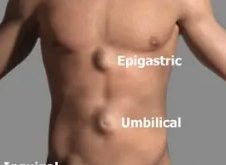

হার্নিয়া কি? পুরুষের হার্নিয়া (Hernia) একটি শারীরিক অবস্থার নাম, যেখানে দেহের অভ্যন্তরের কোনো অঙ্গ বা অংশ, যেমন অন্ত্র বা মেদ, স্বাভাবিক জায়গা থেকে বেরিয়ে গিয়ে ত্বকের নিচে বা অন্য কোনো জায়গায় গিয়েও পড়ে। সাধারণত এই ধরনের সমস্যা পেটে বা কোমরের অংশে হয়। পুরুষদের মধ্যে হার্নিয়া বেশি দেখা যায়, বিশেষ করে বয়স বাড়ার সাথে সাথে, অথবা শারীরিক চাপের কারণে। পুরুষের হার্নিয়ার …